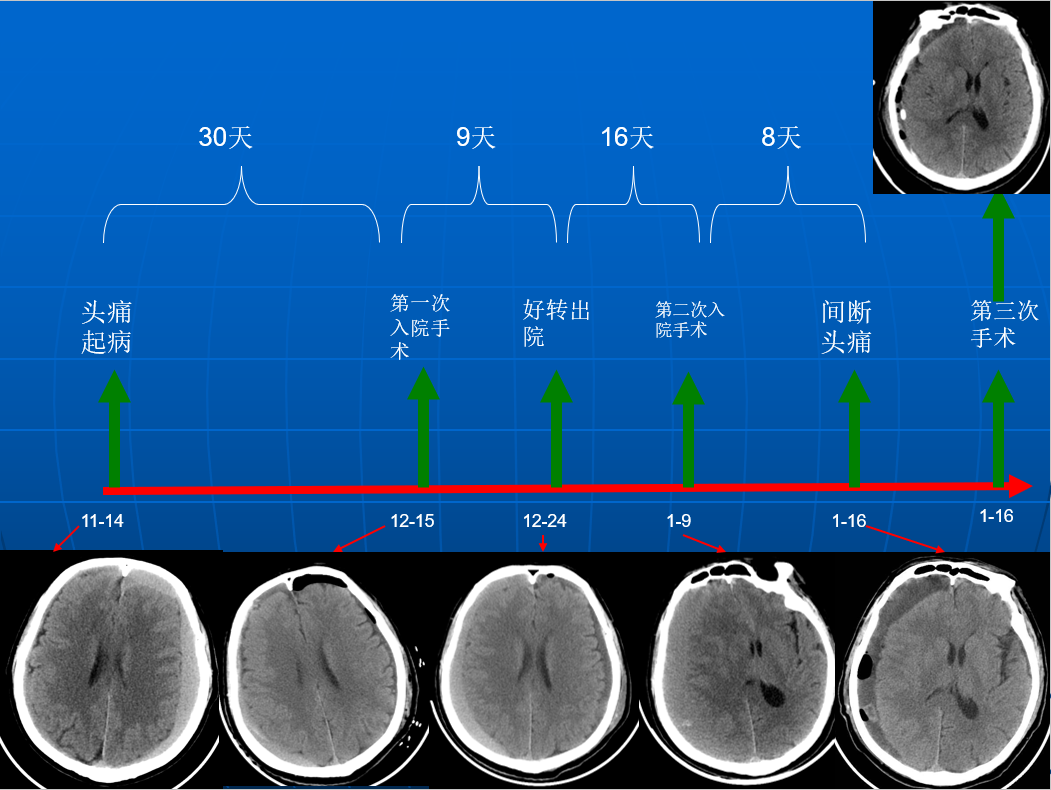

主诉:间断头痛2个月。

患者约2个月前无明显诱因(否认外伤史)间断出现头痛,头痛为胀痛,左侧较明显,恶心未吐,食欲、睡眠尚可,未予特殊诊治,1个月前患者头痛逐渐加重,思睡,反应略迟钝,行头部CT检查示“慢性硬膜下血肿(双侧)”,于2018年12月15日行颅骨钻孔引流术(左)。术后9天患者恢复良好出院。出院后2周于2019年1月9日患者头痛再次加重,伴有反应迟钝,走路困难,疲乏无力再次就诊,头部CT示“慢性硬膜下血肿(右侧)”,当日再次行颅骨钻孔引流术(右)。术后患者一般状态逐渐好转,无抽搐,无尿便失禁。

2018年12月14日第一次入院

自诉偶有头痛,生活自理。查:神志清,反应迟钝,少语,血压160/95mmHg,颈软,右侧肌力IV级。

2018年12月16日术后第一日

自诉头痛明显缓解。查:神清语明,血压145/85mmHg,颈软,四肢肌力V级。

2018年12月24日出院当日

自诉偶有头痛,生活自理。查:神清语明,血压135/85mmHg,颈软,四肢肌力V级。

2019年1月9日第二次入院

近3天头痛明显,生活严重受限。有过尿失禁。查:神志清,反应迟钝,走路不稳,血压160/95mmHg,颈软,左侧肌力III级。

2019年1月13日

间断头痛明显,生活基本自理。查:神清语明,血压150/90mmHg,颈软,左侧肌力V-级。

2019年1月16日

间断头痛明显,生活基本自理。查:神清语明,血压145/90mmHg,颈软,左侧肌力V-级。

术后情况

术后当日(2019年1月16日)

术后3天(2019年1月18日)